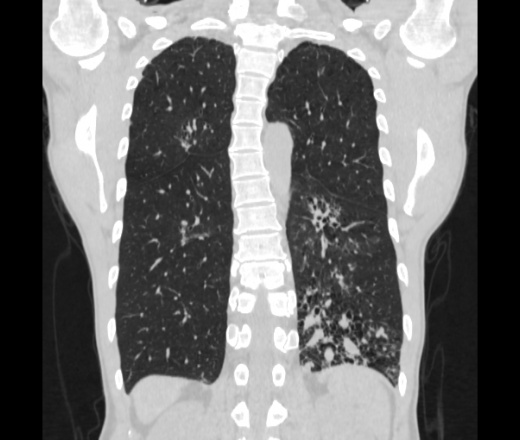

Мужчина пенсионного возраста. Цель назначения КТ ислючение зла в левом легком. Вижу тракционные бронхоэктазы с рубцовой эмфиземой по периферии, скорее всего БЭБ в стадии обострения. Дивертикулы трахеи. Выложил из за того что есть доля сомнения в отношении исключения зно3, немного смущают линии похожие на Керли.

Единственно, не сказал бы, что это тракционные бронхоэктазы, ну, и про линии Керли не вполне понял.

Ну да. Выразился не правильно. На фоне легочного рисунка усиленного линии похожие на септальные, не знаю как называются, при интерстиц.отеке похожие

На мой взгляд, это не главное, указал бы в описании - локально утолщен междольковый интерстиций, и всё